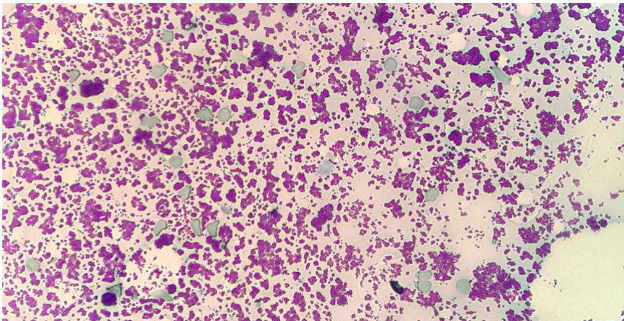

L’esame citologico delle neoformazioni surrenaliche d’altra parte ha dimostrato una elevata accuratezza (90-100%) nella distinzione tra proliferazioni corticali (imagine in alto) e midollarii-feocromocitoma (immagine in basso). Sebbene non permetta con certezza di differenziarne forme maligne da benigne, il conoscere anticipatamente se una neoplasia sia corticale o midol

lare, permette al clinico di prendere possibili precazioni in caso di chirurgia, che potrebbe scatenare crisi ipertensive nel caso di un feocromocitoma.